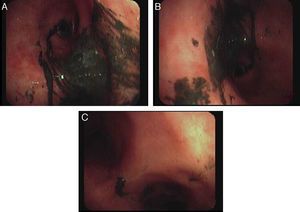

The photograph (Fig. 1) is a view of the flexible fiberoptic bronchoscopy performed via the orotracheal tube 24h after admission, showing diffuse presence of a blackish gelatinous substance adhered to the tracheobronchial mucosa (corresponding to soot deposits) that were difficult to aspirate despite repeated washing with saline solution, along with significant endobronchial edema.

In our patient, fiberoptic bronchoscopy was both diagnostic, ruling out additional complications, such as endobronchial burns or infection of respiratory secretions, and therapeutic, assisting in the removal of the soot deposits, thus preventing the future formation of synechiae caused by the deposits in the endobronchial tract.